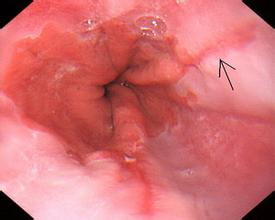

(4)Barrett食管 長(zhǎng)期慢性胃食管反流,可使下段食管的鱗狀上皮被化生的柱狀上皮所代替,成為Barrett食管,以增強(qiáng)抗酸能力。Barrett食管可發(fā)生消化性潰瘍,亦是食管腺癌的主要癌前病變。